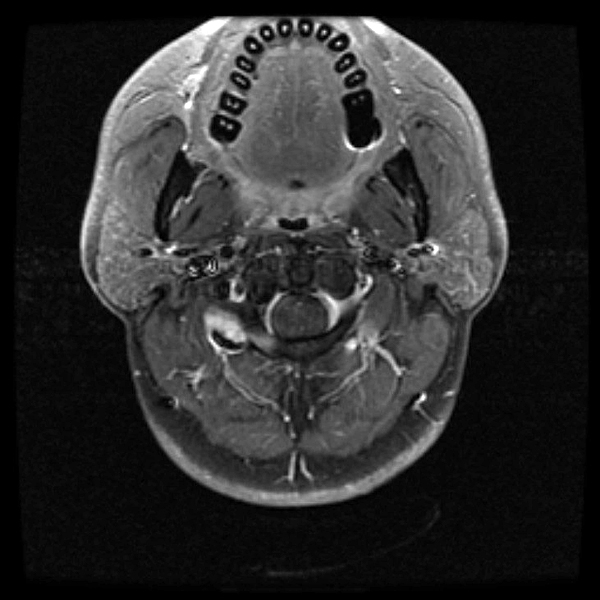

once i got back home and checked out my scans in osirix (the mac os x application to view DICOM medical imaging slides), i was blown away. talk about invasive: you haven't seen intimate until you've looked at photos of the inside of your body. the coolest part is since the scans were done in cross-sections, i can animate the scans so it looks like the beam is passing through my neck and head (all 800+ images). i've always known that inside my body was all sorts of muscles and veins and organs, but i guess i was hoping for something less messy, maybe circuit boards and memory chips instead. i know MRI's were first used in the late 60's, but this is my first time experiencing the technology in-person and it's pretty amazing. talk about futuristic! to be able to see with so much detail the insides of my body without having to cut me open! if scientists can do this, what else can they do? my only regret is they only imaged me from my shoulder up. i'd love to have a full-body scan. maybe i can fake some sort of internal injury and get my doctor to okay the procedure. i recommend anyone who's never had an MRI done to do so when they have the chance.